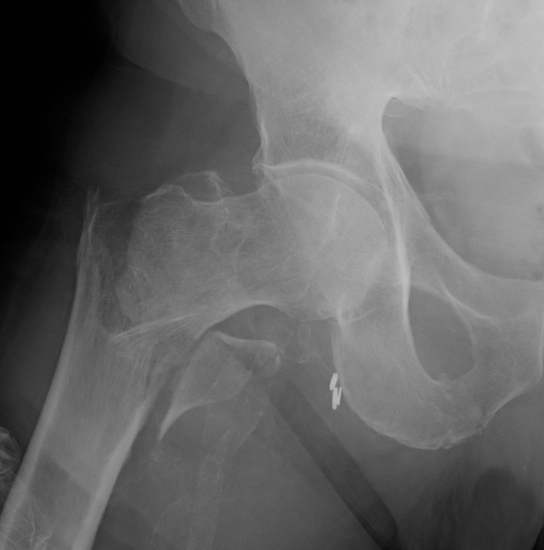

Type II Reverse Oblique Type

Inherently unstable - tendency of femoral shaft fragment to shift medially

Reverse oblique fractures

Stability

Depends on medial cortical reduction

Unstable (AO 31.A2 + 31.A3)

- intact lateral wall

- posteromedial cortical fracture

- reverse oblique

- subtrochanteric extension